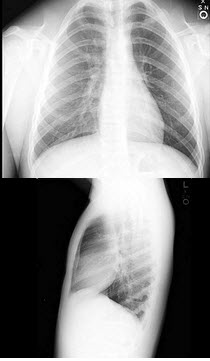

75、单项选择题

男,20岁,胸痛、身材矮小,结合图像,最可能的诊断是()

A.马方综合征

B.颅锁骨发育不全

C.成骨不全

D.软骨发育不全

E.特发性骨质溶解症